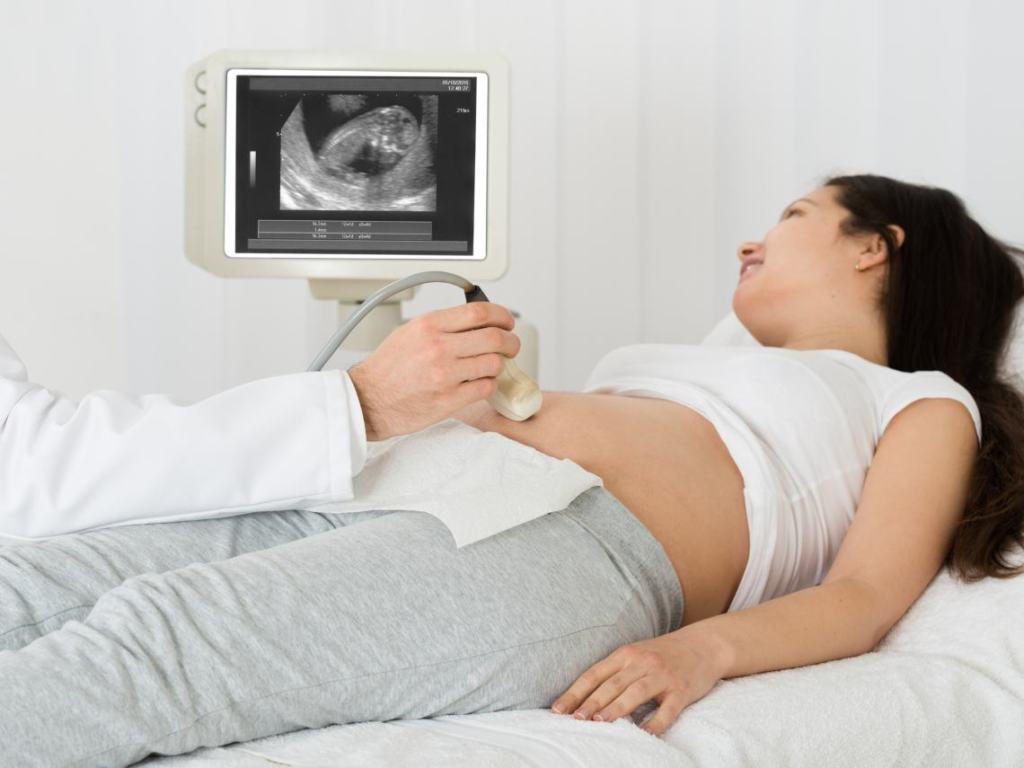

Producido tanto por la futura mamá como por su bebé, y posteriormente reabsorbido por él, el líquido amniótico se convierte en el reflejo de los buenos intercambios entre la madre y su bebé y, también, del buen desarrollo de este último. De ahí que, con cada visita, el médico esté muy atento al volumen existente de líquido amniótico a través de las ecografías.

¿Cómo se diagnostica?

Un aumento de peso repentino, o la aparición de edemas suelen ser también señales de advertencia.

En cualquier caso, la ecografía será finalmente útil para confirmar el diagnóstico. Para ello, el especialista mide las áreas negras que encontramos en la pantalla, y que se encuentran ubicadas alrededor del bebé: son las que se corresponden con el líquido amniótico. Así, con estas diferentes medidas, puede establecer el índice amniótico. A partir de ahí puede hacer el diagnóstico: hidramnios moderado o hidramnios severo.